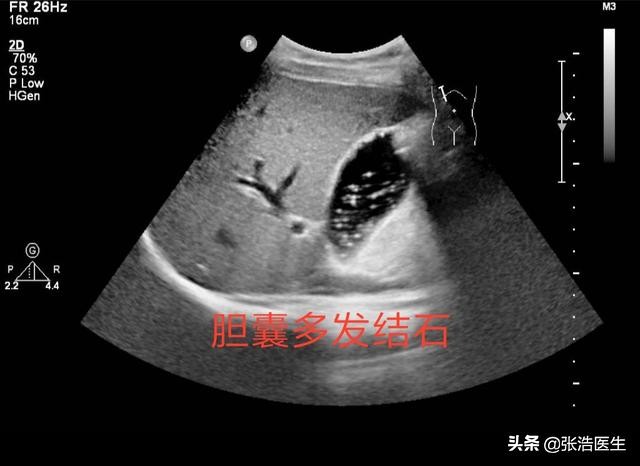

胆囊是消化器官,所分泌的胆汁也是和消化有关,所以如果出现胆囊的问题,首先表现出来的就是消化系统的症状。例如恶心、嗳气、反酸、腹胀、胃部灼热感、呕吐、厌食油腻等。如果是急性的胆囊炎、胆结石,还会伴有胆囊点的疼痛,发热等表现。